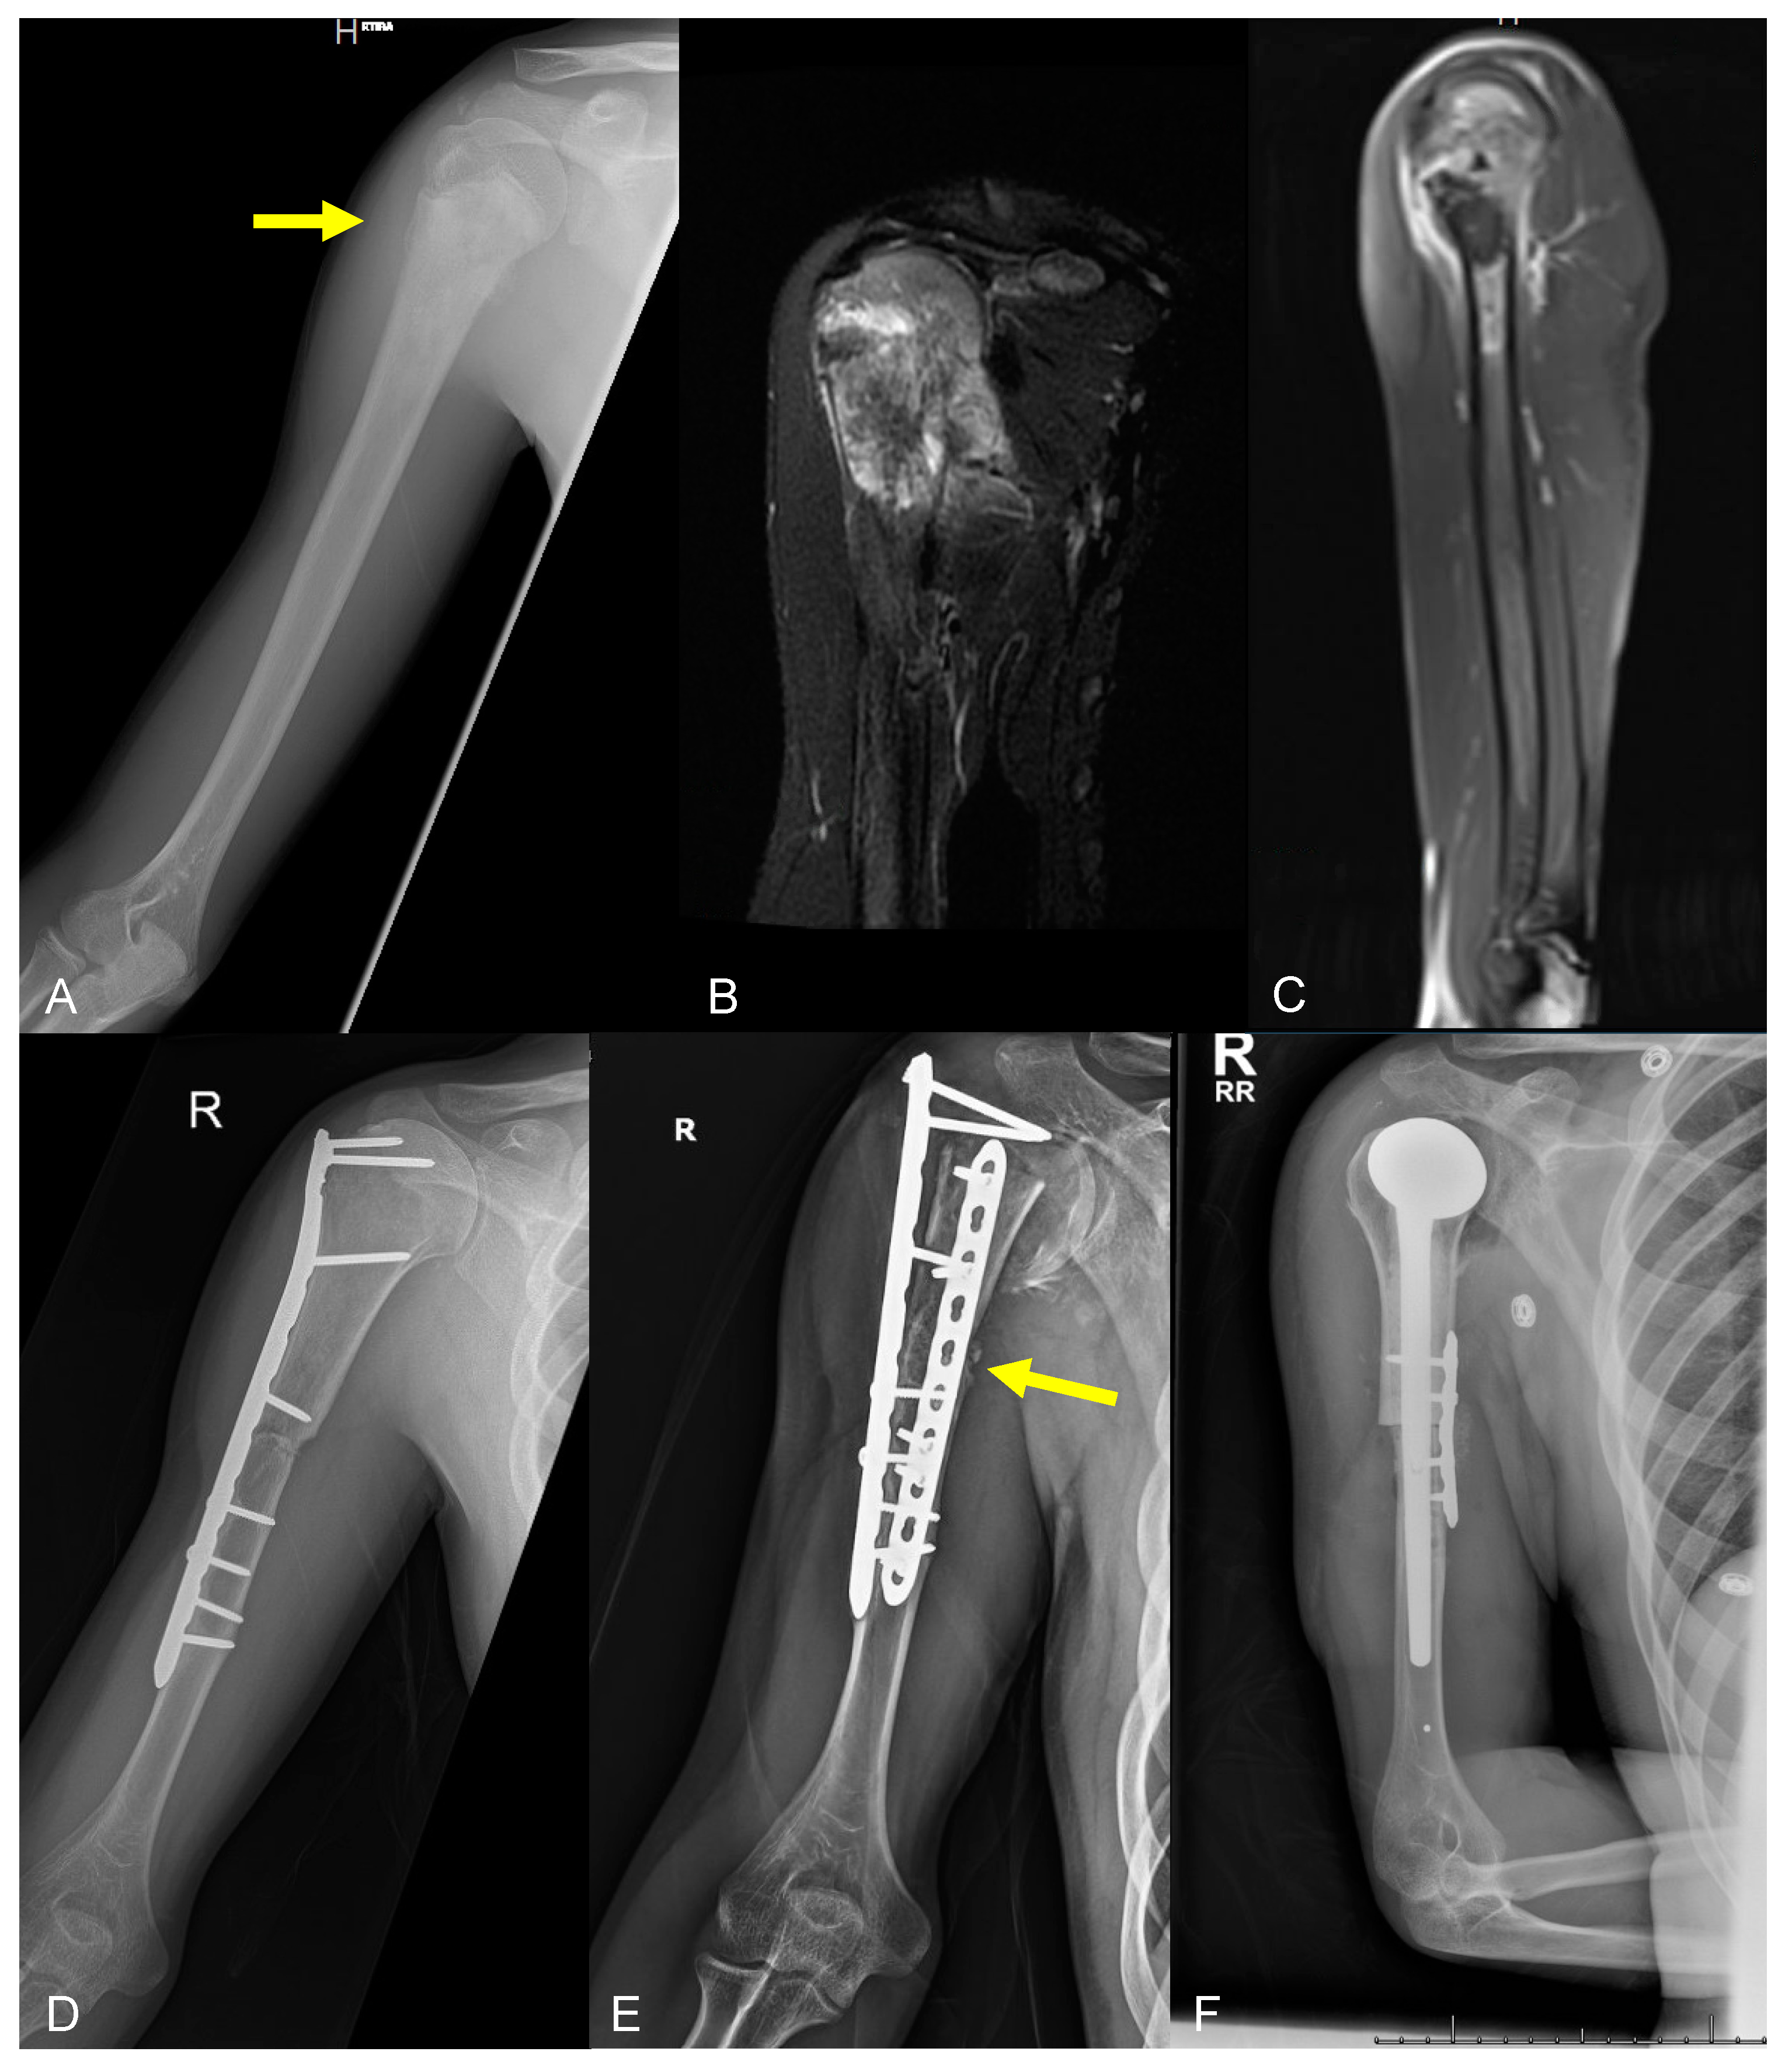

1. Introduction

2.2. Type 2 Failures—Loosening and Nonunion

2.2.2. Graft–Host Nonunion

2.3.2. Structural Failure of Allografts